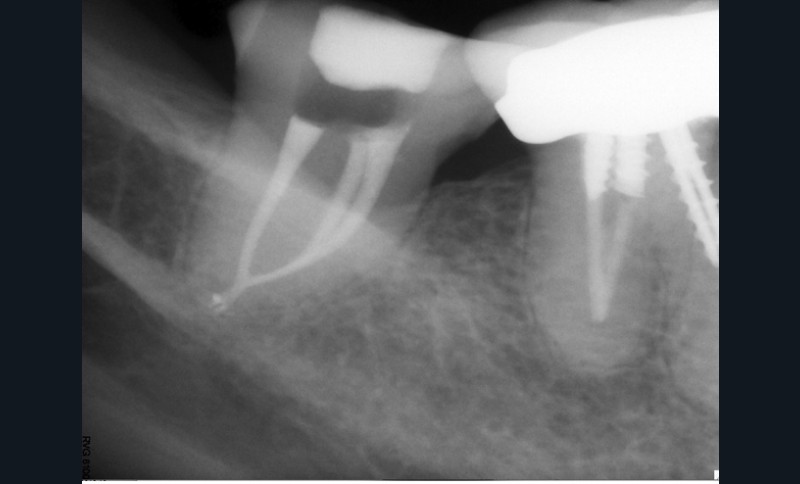

Le laser Erbium s’insère donc parfaitement dans nos principes actuels de traitements mini-invasifs comme activateur de nos solutions d’irrigation (fig. 1a à c).

Endal, en 2011, montrait également, en utilisant le micro CT Scanner, l’insuffisance de nettoyage des isthmes inter-canalaires à nos techniques conventionnelles [19]. L’utilisation du laser Er:YAG devenait alors incontournable dans le nettoyage de ces isthmes et des zones non instrumentées (fig. 2 et 3).